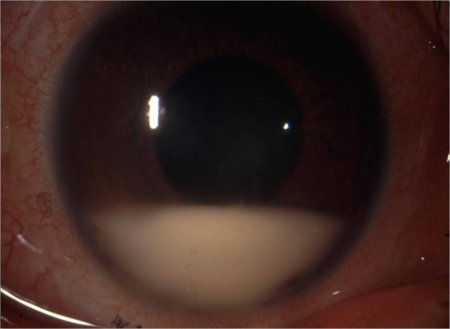

Síndrome de Behçet

Hipópio

Do acervo de Yusuf Yazici, MD

Veja esta imagem em contexto nas seguintes seções: